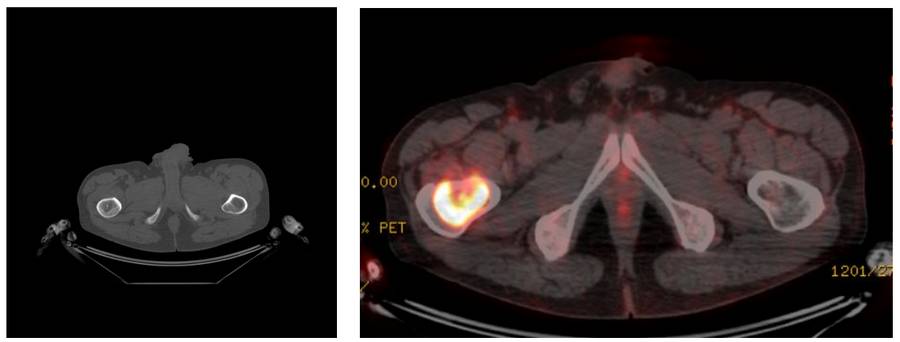

Before the surgery: PET-CT shows cartilage content and increased activity.